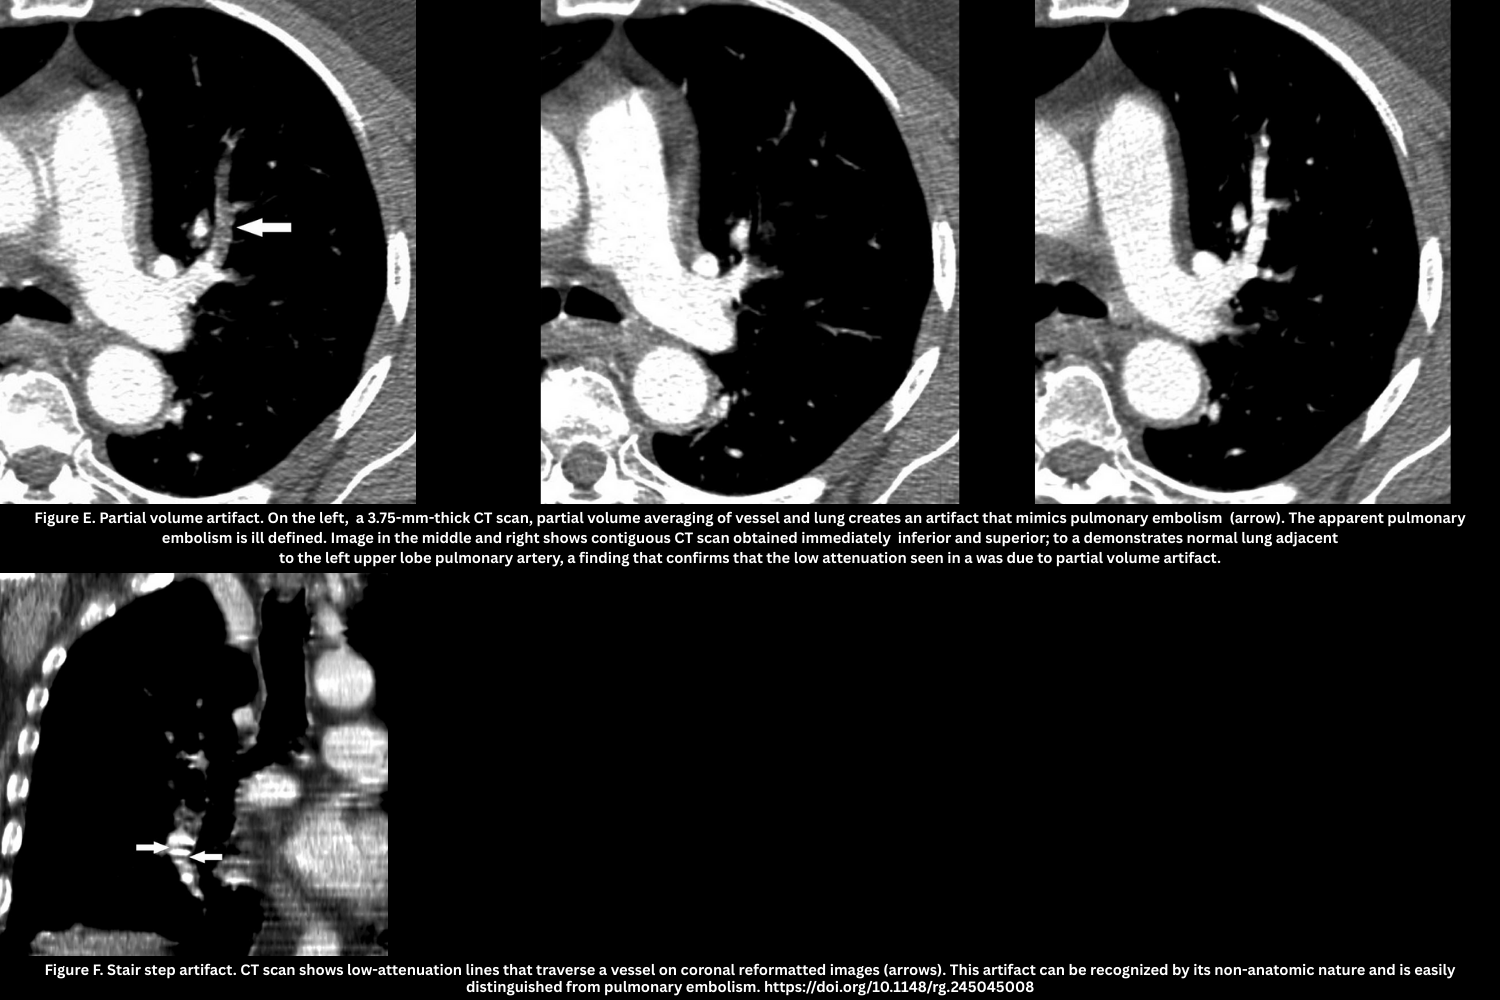

- Partial volume artifact (Figure E)

- Thick slices/axial orientation cause blurred low-attenuation defects.

- Partial volume artifact is caused by the CT system averaging varying tissue densities within a single voxel, leading to blurred edges or incorrect CT numbers at tissue interfaces

- Not reproducible on contiguous slices.

- Stair-step artifact (Figure F)

- The stair-step artifact consists of low-attenuation lines seen traversing a vessel on coronal and sagittal reformatted images and is accentuated by cardiac and respiratory motion.

- Reduced with overlapping reconstructions.